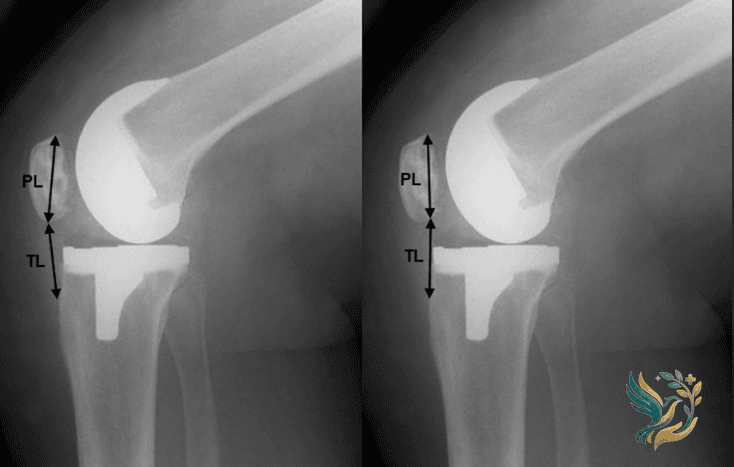

Total Knee Replacement (TKR): The damaged surfaces of the knee joint are replaced with metal and plastic components. Modern implants are designed to replicate the natural movement of the knee, lasting 20-25 years in most patients.

Partial Knee Replacement (Unicompartmental): Only the damaged portion of the knee is replaced. This preserves more natural bone and ligament, resulting in faster recovery and more natural knee movement. Suitable for patients with osteoarthritis limited to one compartment.